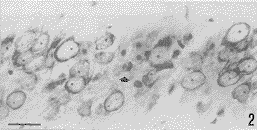

海马CA1区(图2)KA后1d,仅偶见凋亡神经元;KA后3、5d,凋亡神经元的数目渐次增多;KA后7d,凋亡神经元的数目达到最多,同时伴有神经元数量的明显减少。

图2 KA3d后,海马CA1区内的凋亡神经元(↑)。标尺30μm

Fig. 2 An apoptotic neuron in CA1 (↑) ,3d after KA injection.Bar=30μm